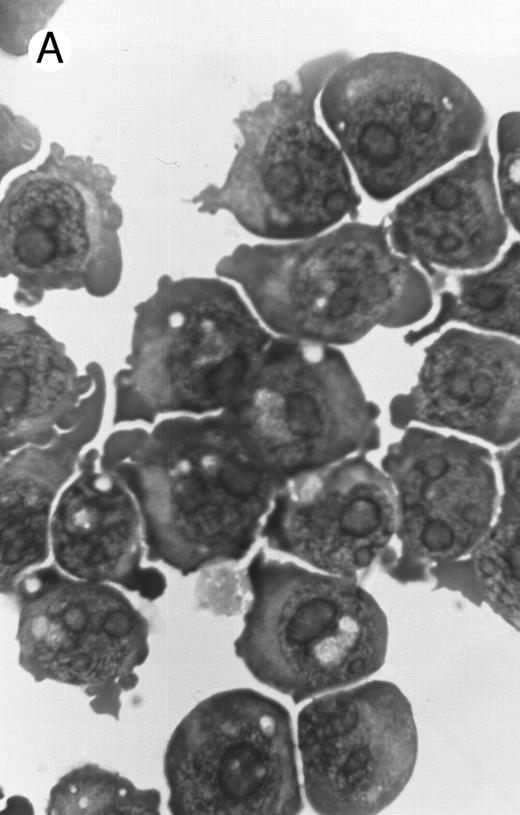

Morphology of PLB-985 cells (A) before treatment and after a 4-day treatment with (B) 1.25% DMSO (differentiation) or (C) 10−7 mol/L 9-cis-RA (apoptosis) (original magnification × 1,000).

We have shown above that activation of both RAR and RXR by 9-cis-RA or by the combination of selective ligands inhibits cell growth and induces cell death in PLB-985 cells. We wished to verify whether these retinoids also induced differentiation of PLB-985 cells before the onset of cell death. Microscopic examination of cell morphology after 4 days of treatment with 9-cis-RA demonstrated no differentiated phenotype (Fig 2C). On the other hand, DMSO-treated PLB-985 cells had a typical differentiated morphology (Fig 2B). We then examined alterations in several cell surface markers, especially those specific for differentiated granulocytes. We contrasted the known differentiation effects of retinoids on NB4 with PLB-985 cells. NB4 and PLB-985 cells express low levels of CD11b and no detectable CD11c, but high levels of CD13.2 44 As previously reported, treatment of NB4 cells with 9-cis-RA increases expression of CD11b and CD11c, and significantly reduces expression of CD13 (Fig 3, bottom), consistent with the differentiation of NB4 cells into granulocytes. Also consistent with their effects on cell growth, the RXR-selective ligand 100153 did not have any effect on the surface marker expression in NB4 cells, but the RAR-selective ligand 100272 induced the same differentiation-specific changes as 9-cis-RA. In PLB-985 cells, DMSO-induced granulocytic differentiation stimulates the surface expression of CD11b44 (and data not shown). In our experiments PLB-985 cells treated with 9-cis-RA did not show any increase in CD11b and CD11c levels. These cells also continued to express high levels of CD13, even at day 4, when the cell counts began to decrease (Fig 3, top). As expected, the selective ligands, either alone or in combination, also did not have any effect on the expression of these markers in PLB-985 cells. These results show that stimulation of both RAR and RXR inhibits growth and induces cell death without differentiation in PLB-985 cells.